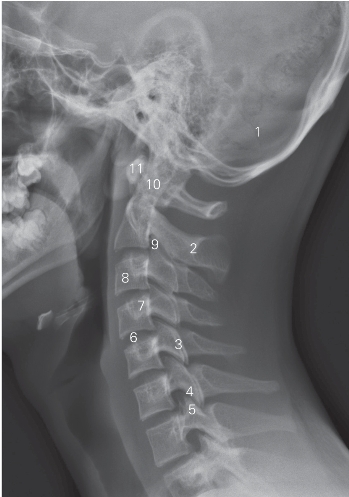

图6-2 颈椎侧位DR平片

1 枕骨 occipital bone 2 第2颈椎棘突 2nd cervical spinous process

3 关节突关节 zygapophyseal joint

4 下关节突 inferior articular process

5 上关节突 superior articular process

6 第4/5颈椎间隙 4th/5th cervical intervertebral space

7 横突 transverse process 8 第3颈椎 3rd cervical vertebra

9 颈2/3椎间孔 2nd/3rd cervical foramen intervertebrale

10 齿状突 odontoid 11 寰椎前弓 anterior tubercle of atlas